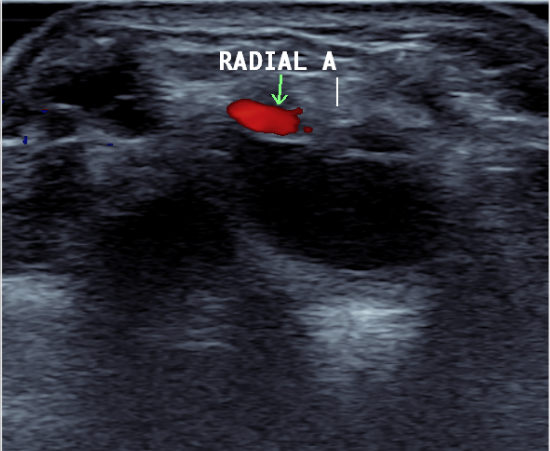

Ultrasound

Volar ganglion with radial artery superficial to ganglion

Volar approach

- between FRC and radial artery

- radial artery at risk

- radial artery variable location relative to cyst

- can use ultrasound to identify radial artery location